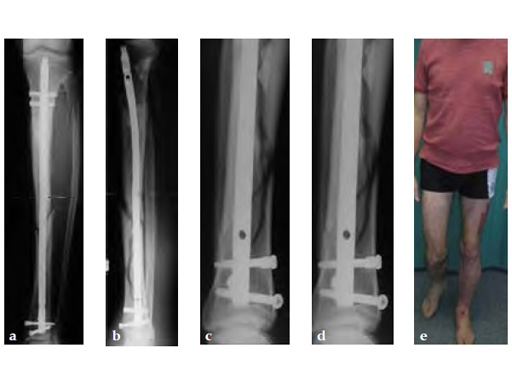

Secondary treatment: insertion of an unreamed intramedullary nail with three ASLS screws inserted distally providing angular stability.

Partial weight bearing started on postoperative day 2 (with 2030kg). The weight was gradually increased over the following weeks. At 6 weeks, the patient was able to fully bear weight even though a high fibula fracture was present and no callus had yet formed. This suggests that angular stable interlocking of the nail markedly enhances stability. The patient was able to bear weight faster than planned and full weight bearing was possible with little pain.

Twelve-week follow-up shows callus formation, and the patient was able to fully bear weight without any pain.

The nail was removed 15 months postinjury as planned. There is good callus formation and proper healing of the tibia fracture.